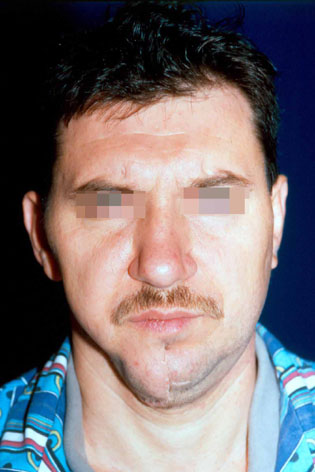

Пациент със злокачествен тумор на дясната част на долната челюст, наложил резекцията й. Възстановена е 1 година по-късно, традиционно чрез собствена костна тъкан от хълбочния гребен - случай на доц. Джоров.

Пациент с тежка травматична деформация на дясната орбита, реконструирана с костни присадки от черепния свод – случай на доц. Джоров.